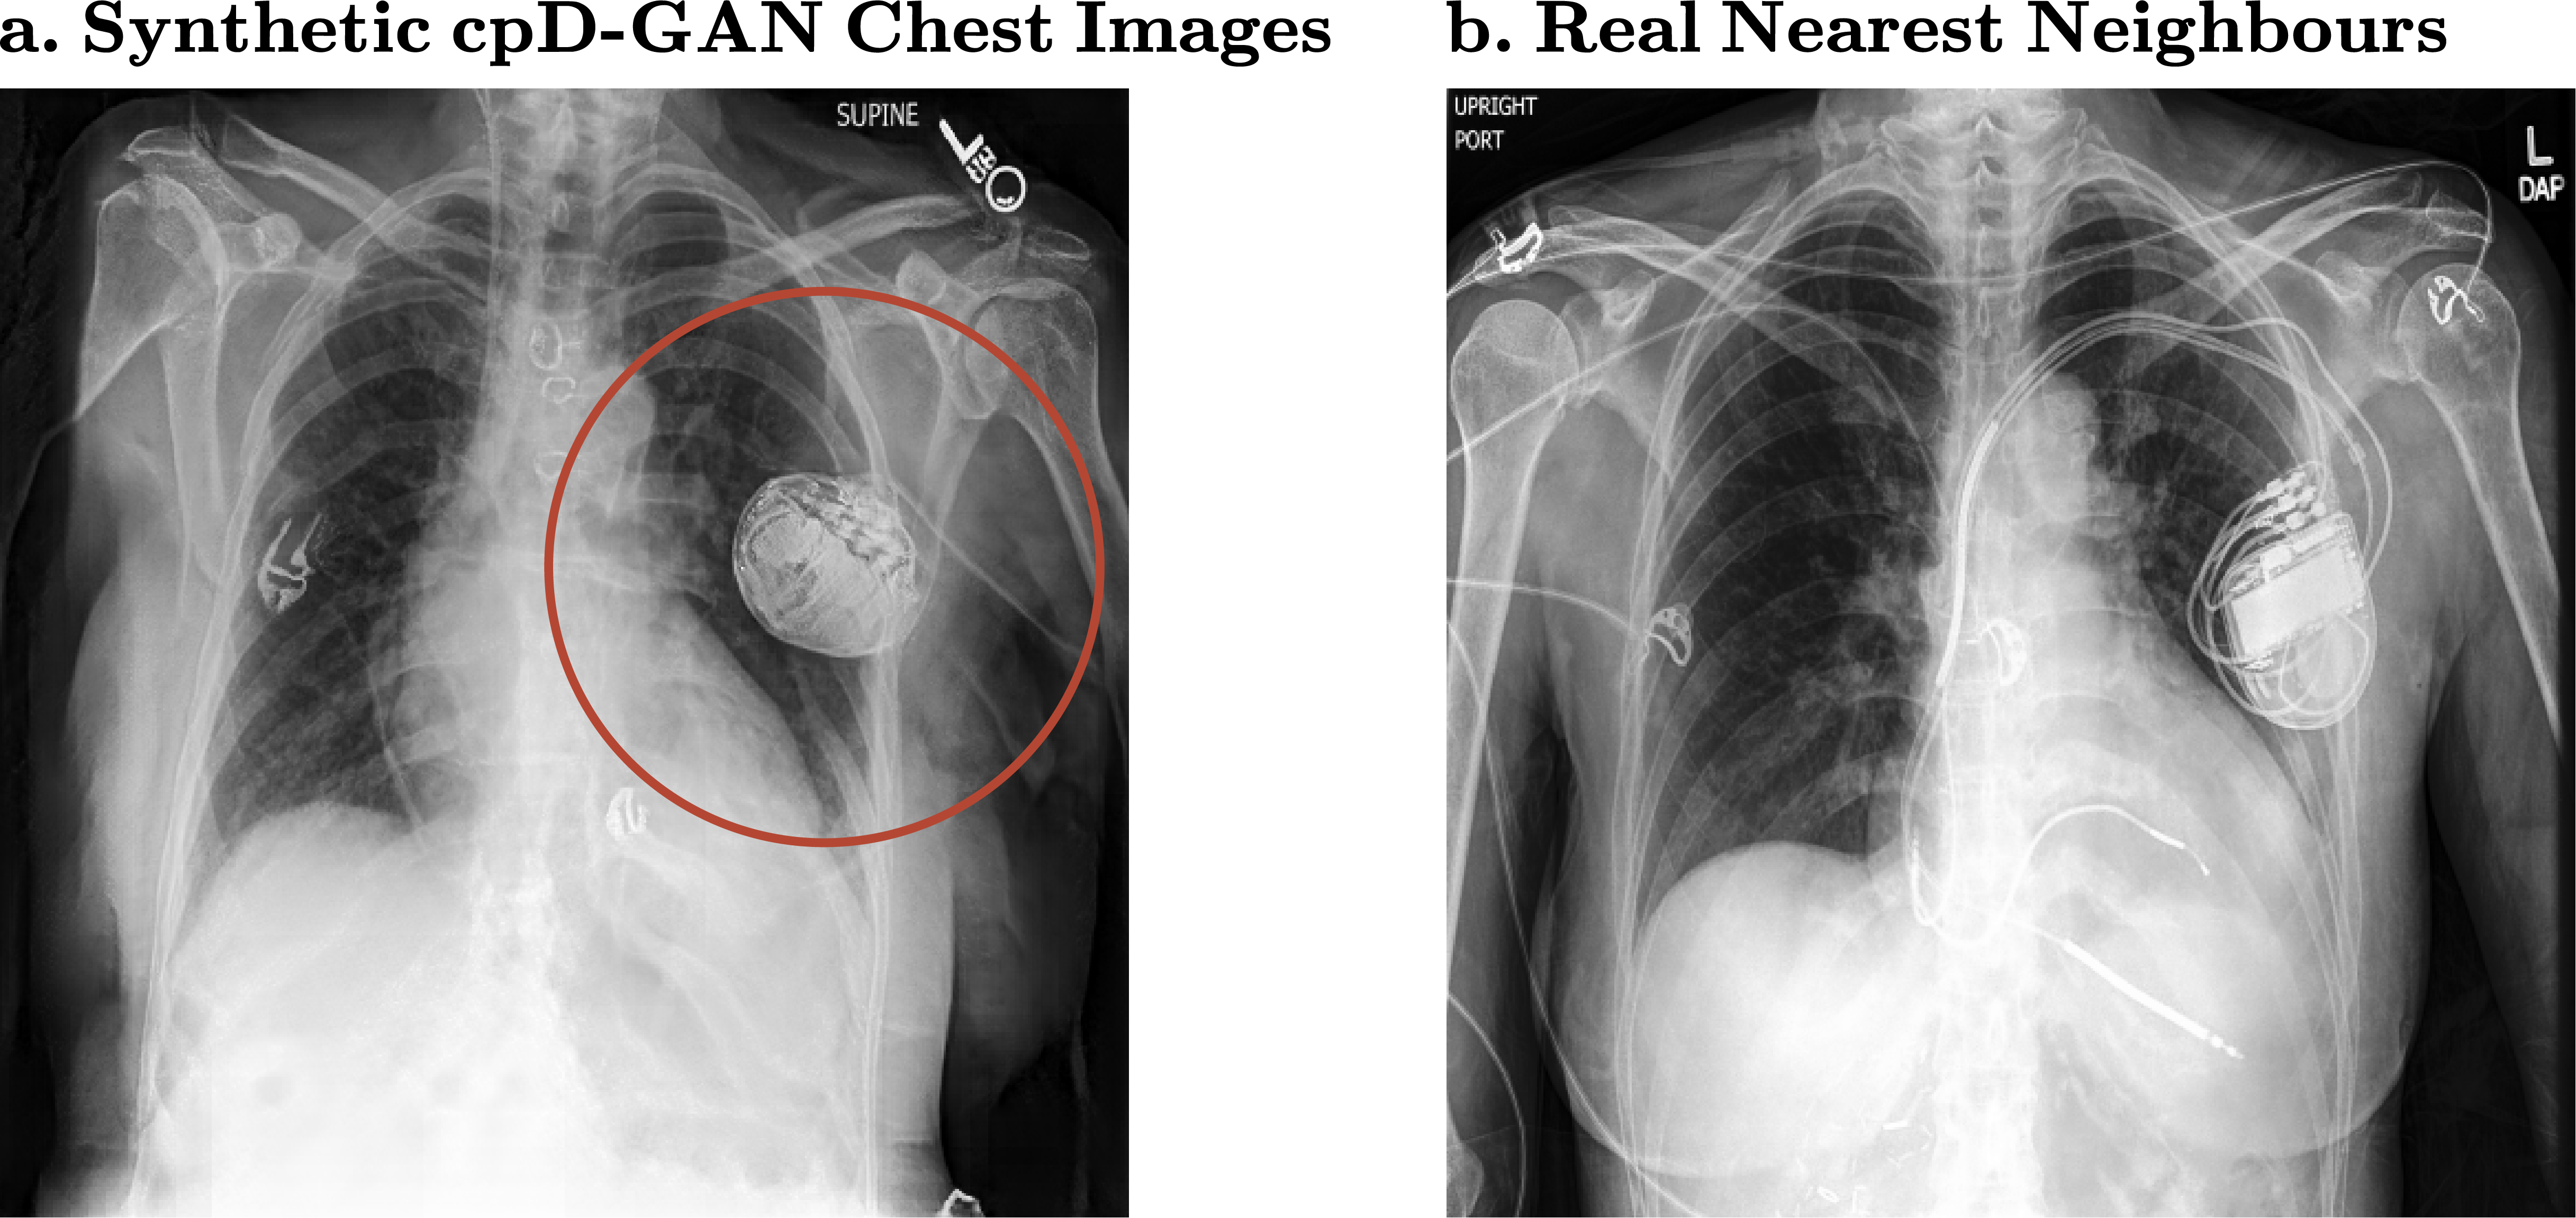

Figure 4:

(a.) Synthetic chest x-ray with artefact and (b.) closest real matching neighbour at a resolution of 512 x 512 pixels

The quality of the chest x-rays in Fig. 3 also appears to be close to the quality of real data, without simply copying training images. However, for the support devices class, we observe visual artefacts in the synthetic x-rays. The GAN model fails to realistically generate tubes and other support devices, such as pacemakers or defibrillators, as shown in Fig. 4. These devices deviate strongly in their visual appearance when compared to the physiological chest outlining and were not accurately learned by the generative model. Crucially, our benchmark successfully captured the drops in visual quality due to the support devices class at higher resolutions.